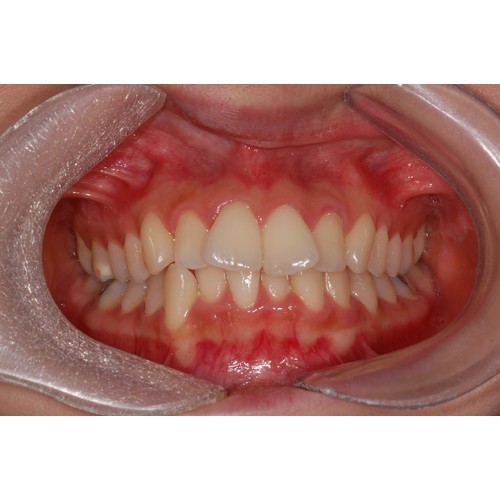

CHUNCHU'S ORTHODONTIC CLINIC# BEFORE_AFTER

춘추치과교정과를 방문해주신 분들의전후 사진을 확인해보세요.